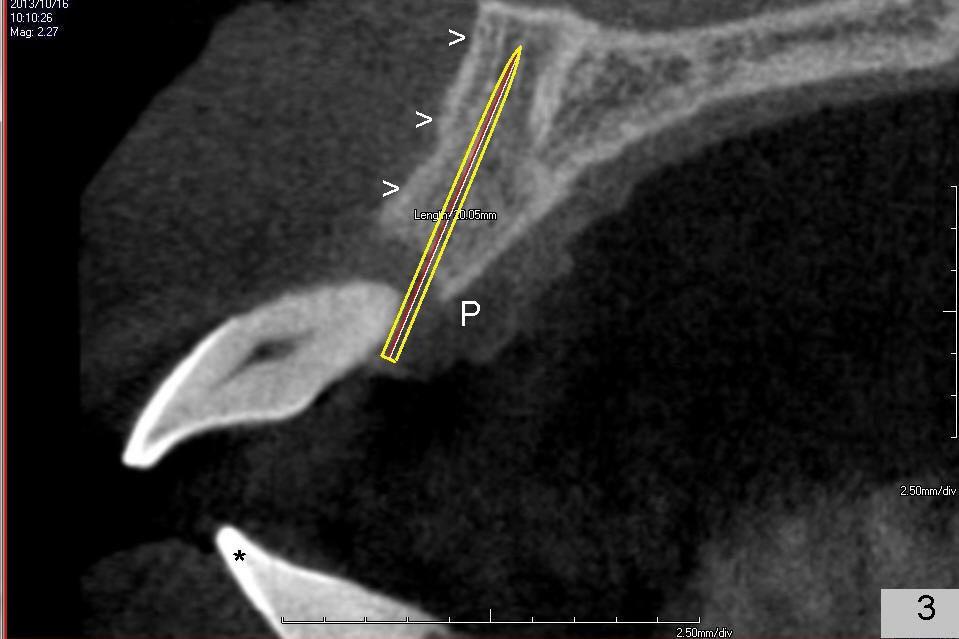

A 49-year-old man has severe chronic periodontitis. The upper central incisors are protrusive and mobile (Fig.1,2: #8,9), but the basal bone is wide and tall (BB in Fig.2). Immediate implants are going to be placed. To avoid malpositioning of the implant, initial osteotomy begins close to the palatal plate (Fig.3: P), while the axis of the osteotomy is parallel to and close to the buccal plate (>). The implant (Fig.4 pink), abutment (red) and the crown (white) will be in a favorable trajectory. To reduce protrusion, the incisal edge of the lower central will be trimmed (compare Fig.3 * and Fig.4 black area).

On the day of surgery, occlusal equilibrium is to be done for the supraerupted, protrusive lower central incisors first. If there is time, scaling and root planing will be done for the lower arch. Temporary abutments will be used to fabricate immediate provisionals. Screws will be used to fix the abutment/provisional complex to avoid cement. The opening for the screw will be closed with cotton pellet and Cavit. How is the result?